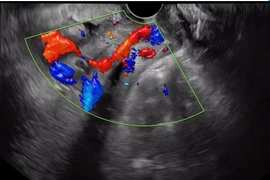

Rau tiền đạo là biến chứng thai kỳ nguy hiểm đe dọa tính mạng mẹ và thai nhi, có thể được phát hiện sớm từ tuần 20 của thai kỳ nhờ vào phương pháp siêu âm thai.

Rau tiền đạo, mạch máu tiền đạo là một biến chứng nguy hiểm trong thai kỳ, đặc biệt nếu không được theo dõi sát sao, nguy cơ chảy máu ồ ạt có thể đe dọa tính mạng mẹ và con bất cứ lúc nào.

Rau tiền đạo có cài răng lược là một bệnh lý nguy hiểm, có khả năng đe dọa tính mạng mẹ và thai nhi, sản phụ cần chú ý thăm khám và quản lý thai chặt chẽ để phát hiện và xử trí kịp thời.

Rau tiền đạo trung tâm, rau cài răng lược là bệnh lý sản khoa nguy hiểm khi bánh rau đâm xuyên qua lớp cơ tử cung, xuyên thành bàng quang, trực tràng.... Bệnh gây ra nhiều biến chứng nguy hiểm, đe dọa tính mạng cả thai phụ lẫn thai nhi.